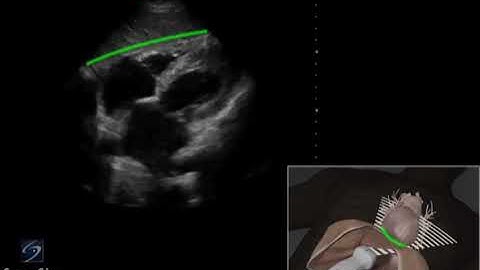

How To: EFAST - Subxiphoid View 3D Video